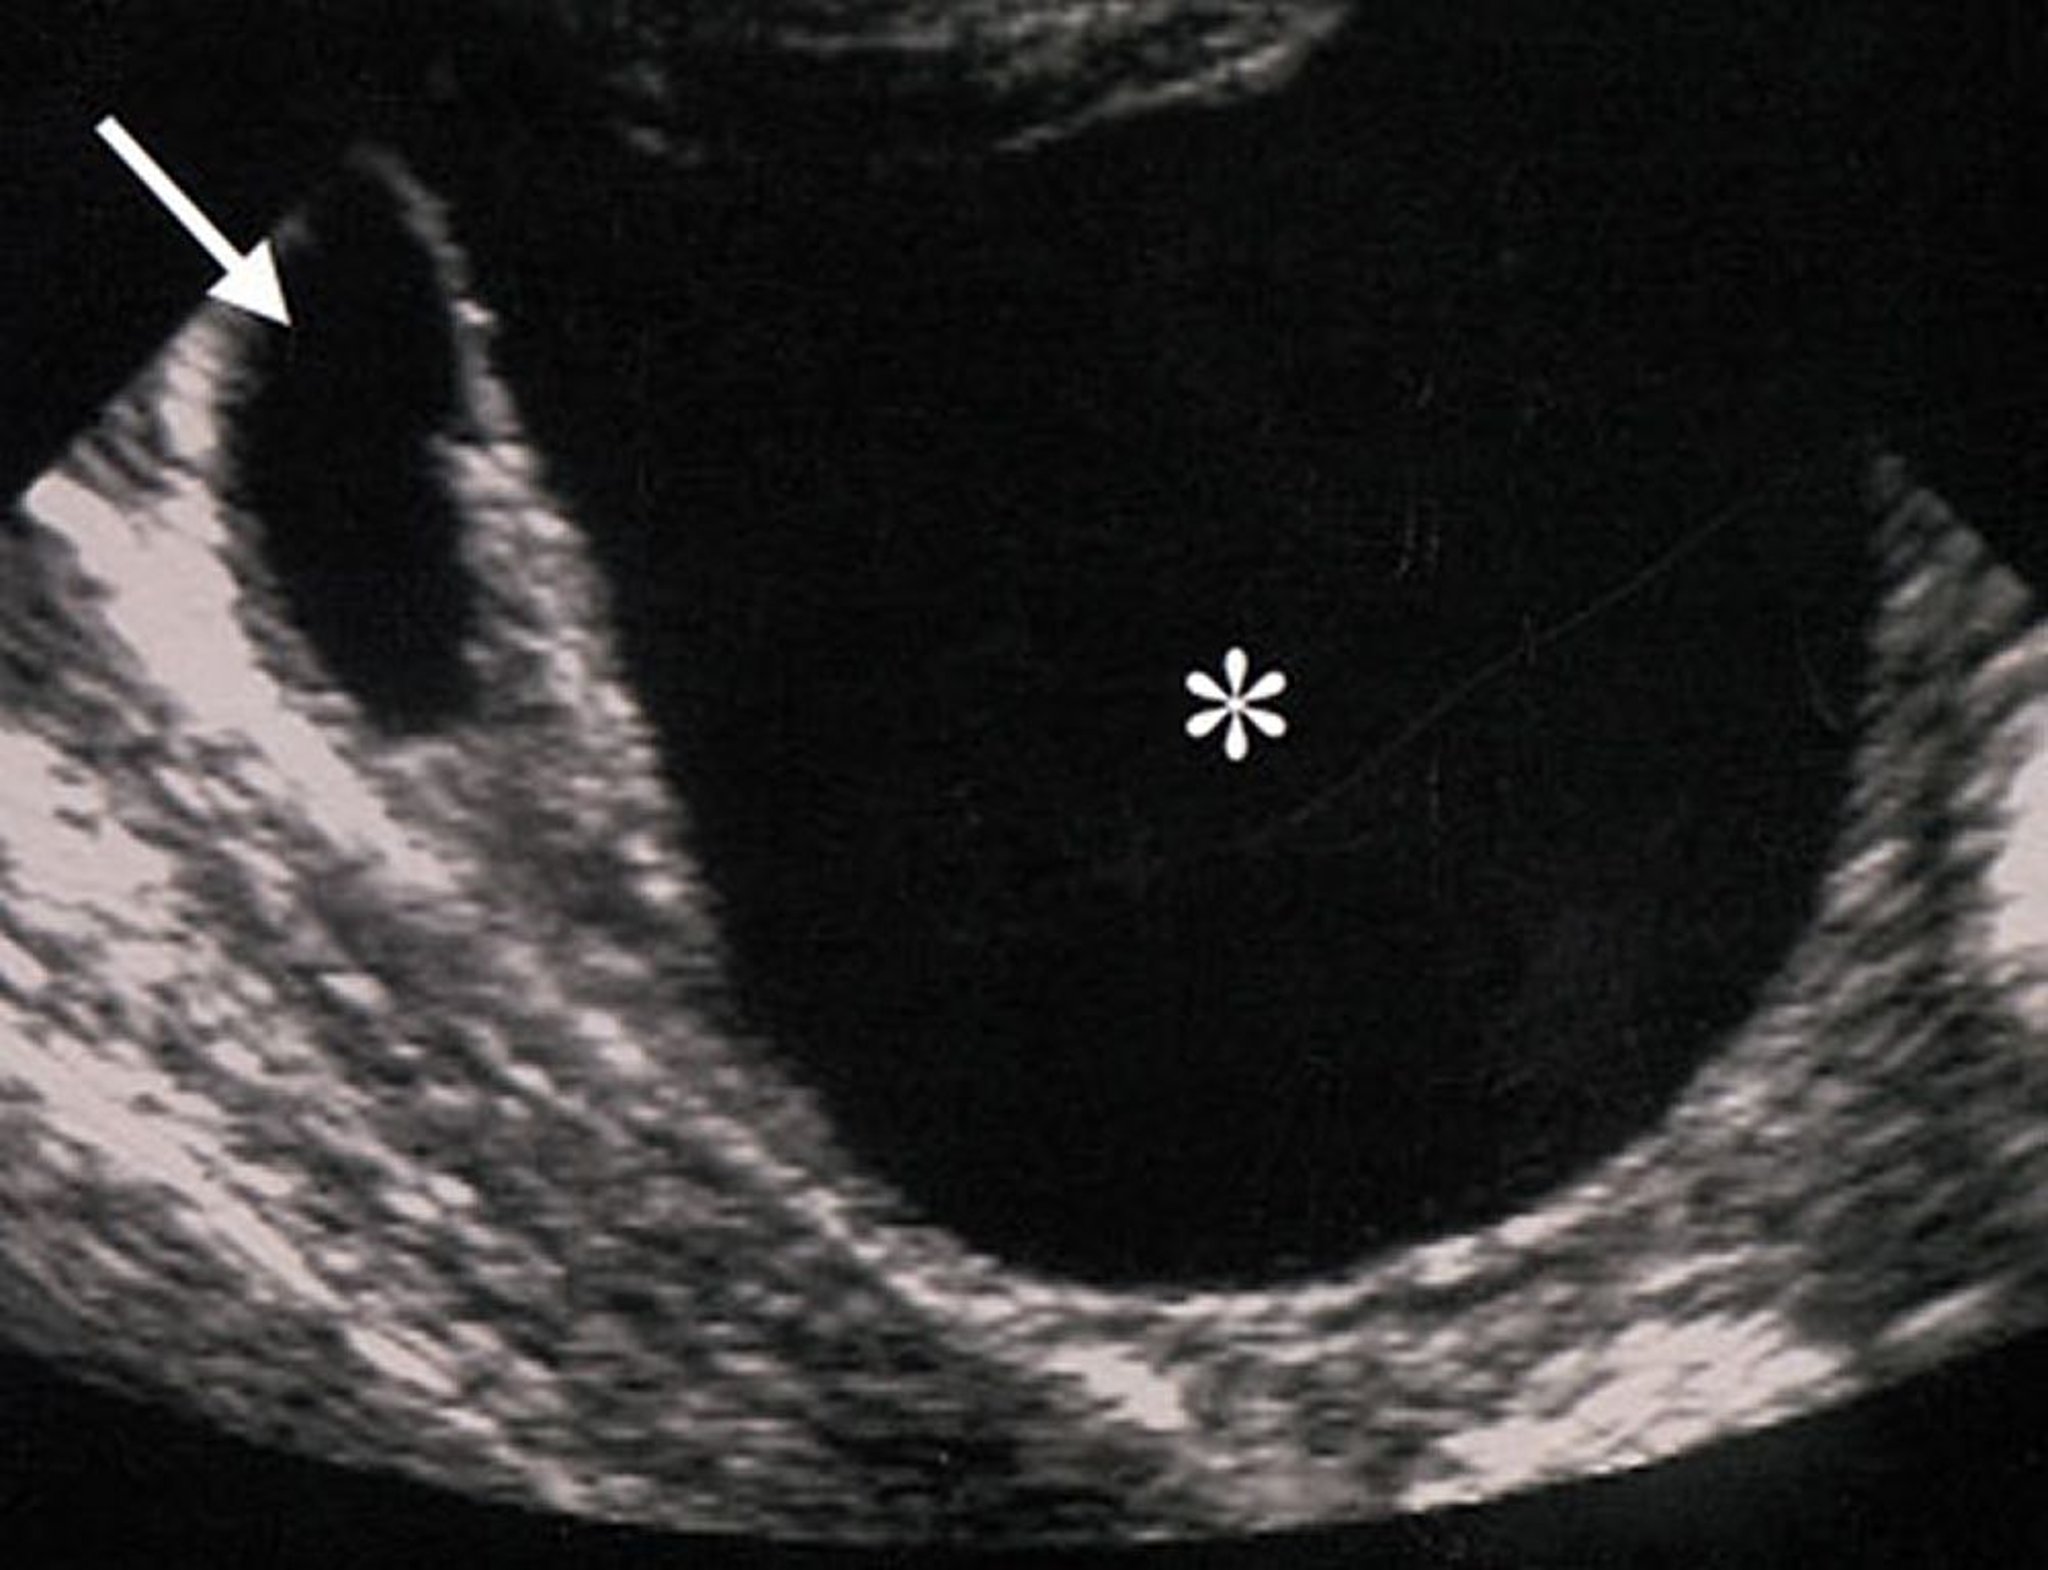

УЗИ доброкачественных опухолевидных образований яичников

Ультразвуковые характеристики опухолевидных образований яичников (отмечены звездочкой), указывают на их доброкачественность. Образование анэхогенное (что говорит об отсутствии твердотелых элементов), правильной формы, с четкими краями, без утолщения стенок или патологических разрастаний.